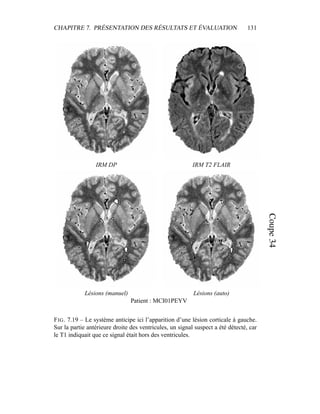

c’est donc sur elle que portera l’analyse lors de la segmentation en tissus et de la

présentation du modèle de volume partiel. Les autres modalités seront utilisées a

posteriori.

4.4 Segmentation en tissus.

4.4.1 Algorithme